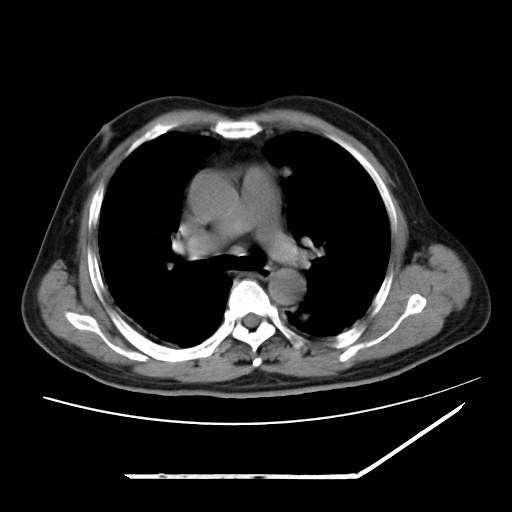

男,57,畏寒,发热

两肺野多发大小不一高密度灶,纵膈内见肿大淋巴结,要考虑转移瘤可能。双侧胸腔少量积液。

双肺多发结节样病灶,部分内见透光区,纵隔内见淋巴结肿大。结核临床如有畏寒,高热,白细胞增高首先考虑迁徙性肺脓肿(多是金黄色葡萄球菌感染)。

注意除外转移瘤。

1)考虑两肺感染性病变(金黄色葡萄球菌肺炎?);建议抗炎治疗后复查排除其他。2)双侧少量胸腔积液。